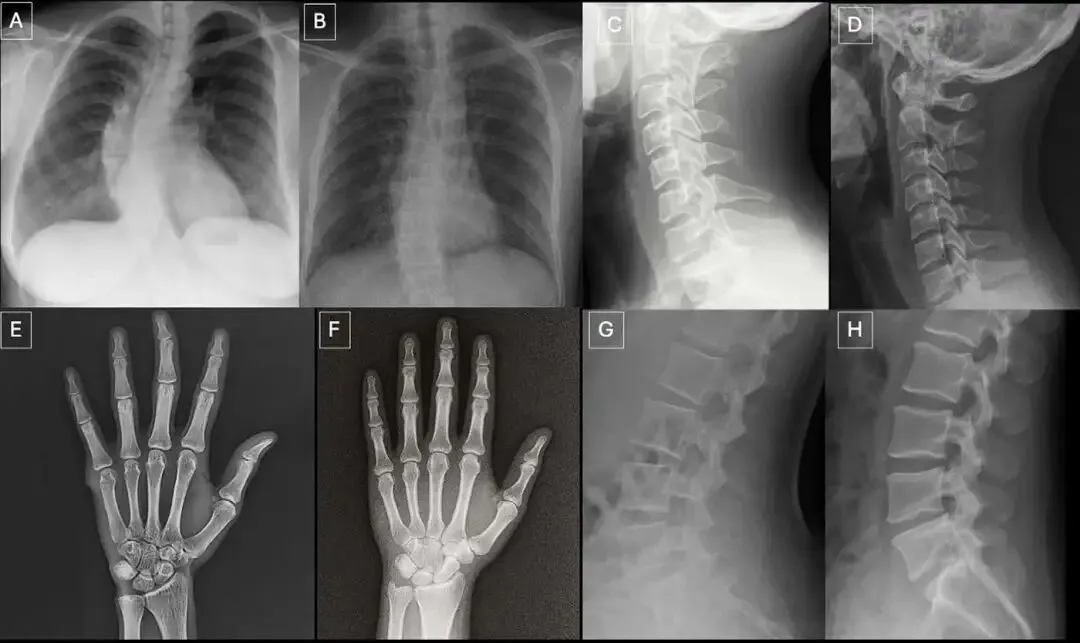

他们首先利用ChatGPT-4o,根据包含解剖部位、投照方式、目标异常(如骨折、肿瘤)等信息的文本提示,生成了77张合成X光片,涵盖胸部、脊柱和四肢。同时,从公开数据库和机构内数据库中匹配了77张真实的X光片,共同组成第一个数据集。

过度的对称性:AI倾向于生成完全对称的解剖结构,例如脊柱完美笔直,除非特意提示“脊柱侧弯”。 均匀的纹理与噪声:真实X光片的颗粒噪声分布是不均匀的,而AI生成的图像噪声往往过于均匀一致。 不自然的软组织纹理:肌肉、脂肪等软组织的灰度过渡有时显得 subtly(微妙地)不自然。 过于光滑的骨骼:骨皮质的边缘异常光滑,厚度均匀,缺乏真实骨骼那种自然的微小不规则和纹理。 “理想化”的骨折线:AI生成的骨折线往往异常清晰、平滑,有时甚至是单皮质的(仅一侧骨皮质断裂),这与真实创伤中复杂、粗糙的骨折形态不同。